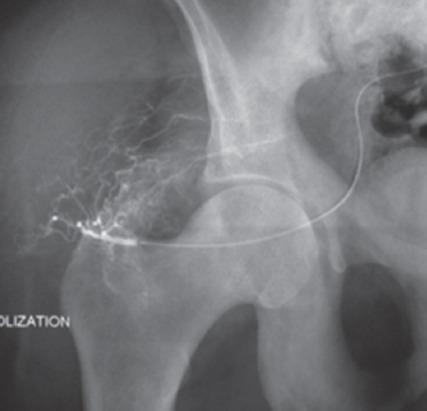

一名 40 岁男性因背痛就诊,经评估诊断为多骨型 PDB。他接受了静脉注射双膦酸盐、钙剂和维生素 D 补充剂治疗。在无症状的 3 年后,他出现了累及髂骨和骶骨的臀肌肿块,活检确诊为 GCT。尝试了系列血管栓塞术,但肿块仍进展,因此进行了手术,切除并刮除病变。2 年后他出现局部复发,伴有大量软组织成分。开始使用地诺单抗(一种 RANKL 抑制剂),目的是降低病变分期。患者在 6 次给药后显示出良好反应,软组织肿块缩小,随后接受了部分 T-1 型内部半骨盆切除术和骶骨刮除术。目前,患者在 15 个月的随访中无症状。